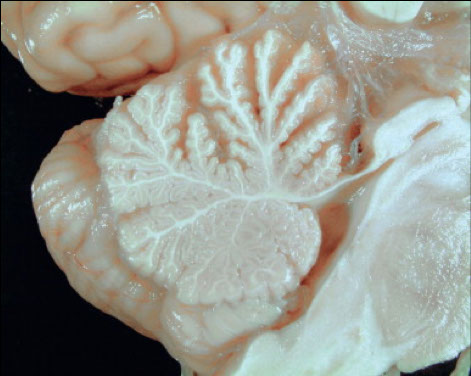

Alcoholic Cerebellar Degeneration

The anterior portion of the vermis (upper portion of figure) is atrophic with widened spaces between the folia